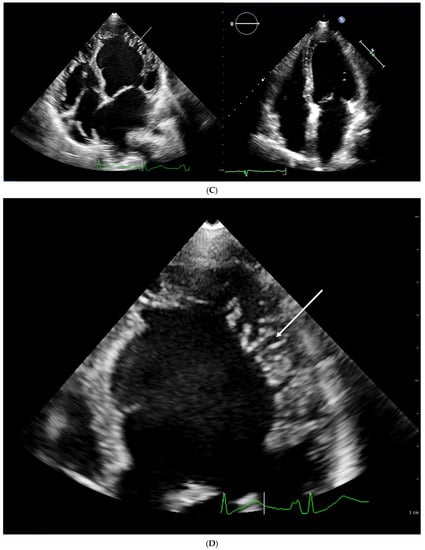

4.1. Echocardiography

| Chin [3] | ECHO | The ratio of the distance from the deepest trabecular recess to the epicardial surface (X) and the distance from the tip of the trabeculation to the epicardial surface (Y) | Long axis, end diastole | X/Y ≤ 0.5 |

| Stöllberger [47] | ECHO | Ratio of compacted and non-compacted endocardium. Presence of at least 3 trabeculations protruding in the left ventricle apically from papillary muscle, presence of the blood flow between trabeculations. | Four chamber, end diastole | NC/C > 2 |

| Jenni [33] | ECHO | Ratio of compacted and non-compacted endocardium. Absence of coexisting cardiac abnormalities, the presence of deep trabeculations, which are filled with blood | Short axis, end systole | NC/C ≥ 2 |